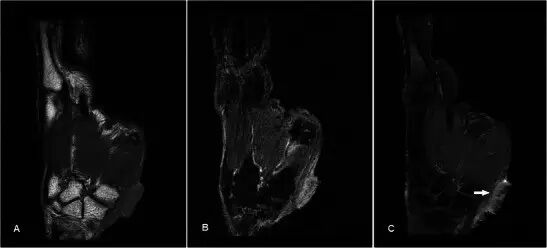

腱鞘囊肿Ganglion cyst 腱鞘囊肿是手部和手腕区域中最常见的肿块[2]。他们往往发生在年轻的成年人,女性发病更加频繁。它们被认为代表由慢性刺激引起的结缔组织的退化[3]。最常见的位置是在手腕的舟月关节背部。较不典型的部位包括手腕的掌侧从桡骨-舟骨( radio-scaphoid )或舟骨-大多角骨(scapho-trapezial)关节,在相对于掌指关节,以屈肌腱和远端指间关节[4]。MR显示了流体信号的良好外切的单个或多腔的损伤,但是信号可以根据蛋白质含量的量而变化(图1)。可以看到囊的轻度边缘增强,但是通常没有内部内容物的增强。鉴别诊断包括滑膜囊肿和其他囊性病变,例如表皮囊肿。

图1.24岁的女性腱鞘囊肿,呈现一个缓慢成长,坚定,无痛的手肿大约6个月。 (a)T1w序列显示在均匀低信号的大鱼际肌组织内的平滑、良好边缘病变。 (b)T2w-FS序列上的病变是高信号的。 没有看到侵入相邻结构。 (c)有最小的边缘增强,没有显着的内部增强(箭头)